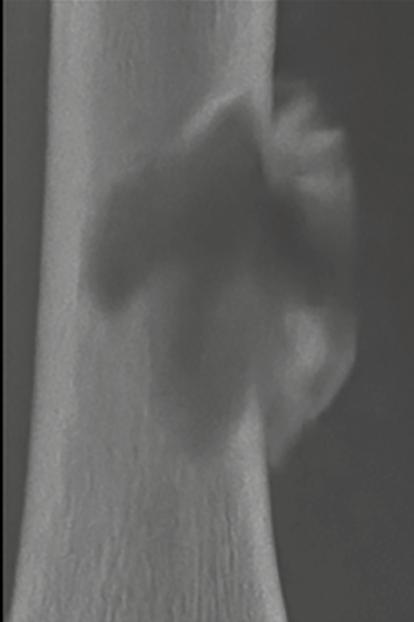

En contraste, una zona de transición amplia, mal definida y con márgenes imprecisos suele indicar un crecimiento óseo rápido y agresivo. Este patrón es característico de muchos tumores óseos malignos, como los sarcomas primarios o las metástasis en adultos mayores. No obstante, es fundamental recordar que algunas lesiones benignas también pueden presentar un comportamiento radiológico agresivo. Tal es el caso de las infecciones óseas y el granuloma eosinofílico, dos condiciones que deben incluirse en el diagnóstico diferencial de lesiones con márgenes mal definidos. A pesar de su naturaleza no neoplásica, pueden simular tumores malignos por su capacidad de destruir la cortical ósea o generar reacciones periósticas llamativas. En la Figura 3 se muestran ejemplos de estas presentaciones agresivas pero benignas.

Figura 3. Una zona de transición amplia indica malignidad o infección o granuloma eosinofílico. 1. Osteosarcoma. 2. Osteomielitis. 3. Granuloma eosinofílico. Tomada de: Jan van der Woude R, Smithuis R. Bone tumors. Differential diagnosis [Internet]. 2010 [consultado 2025 oct 13]. Disponible en: https://radiologyassistant.nl/musculoskeletal/bone-tumors/differential-diagnosis